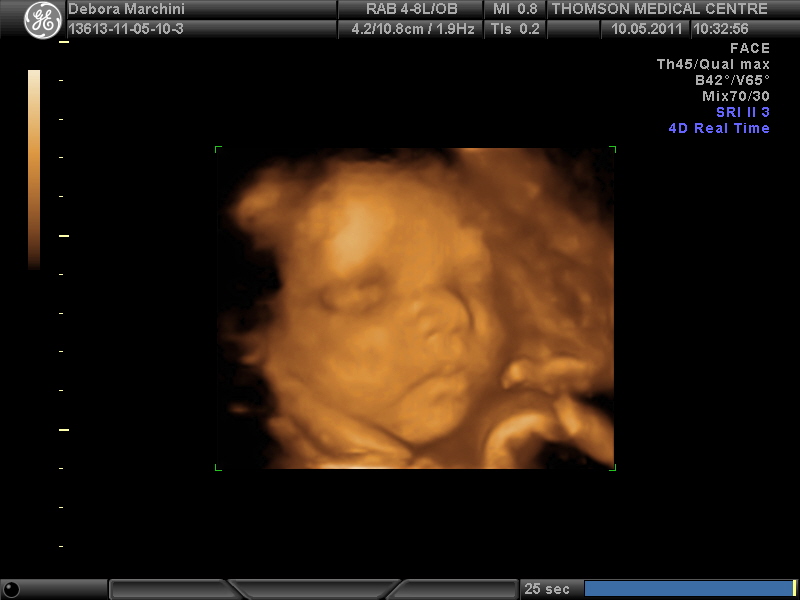

3d 4d Echo Voorbeelden

26 Mei 2015 25 Weken 4d Echo Rdvulture Com